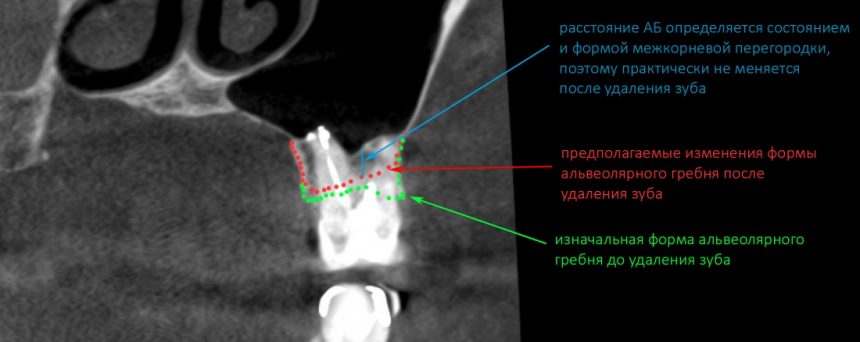

Кстати, обрати внимание на ширину альвеолярного гребня (левая картинка). Она чуть меньше 3 мм. Это объясняет, почему я засомневался в возможности установки имплантатов одновременно с остеопластикой. Понятно и без КЛКТ.

Возвращаемся к основной операционной области. Еще раз посмотрим на альвеолярный гребень, поофигеваем от его ширины и моих грандиозных планов: